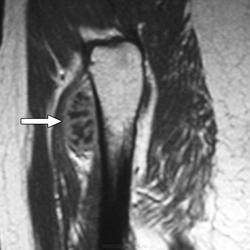

Юкстакортикальная хондросаркома (син.: паростальная хондросаркома, периостальная хондросаркома)—довольно редкая злокачественная опухоль, которая составляет 2 % от общего числа хондросарком. До 80 % больных находятся в возрасте старше 20 лет и лишь 1/3 из них предъявляют жалобы на боль. Опухоль постепенно увеличивается в размерах в течение многих месяцев. Наиболее частая ее локализация — метафизарая часть бедренной кости. Реже поражаются плечевая кость, кости таза, очень редко —ребра и кости стопы. Рентгенологическая картина напоминает то, что характерно для периостальной хондромы с ее блюдцеобразным вдавлением и склерозированным краем в пораженной кости. В некоторых случаях обнаруживается частичное разрушение кортикальной пластинки, и тогда граница опухоли с окружающей костью становится расплывчатой. На границе опухоли с непораженной костью часто видна треугольная склеротическая шпора. Юкстакортикальная хондросаркома часто достигает больших размеров: 7—17 см в диаметре. При осмотре невооруженным глазом юкстакортикальная хондросаркома имеет вид дольчатого новообразования беловато-серого цвета, полупрозрачного на разрезе. На поверхности разреза часто встречается очаговое обызвествление. Подлежащая кортикальная пластинка разрушена и замещена склерозированной костной тканью. Опухоль никогда не проникает в костномозговой канал, хотя под надкостницей она разрастается очень широко.

Под микроскопом отдельные дольки, состоящие из зрелого гиалинового хряща, окружены тонкими фиброзными прослойками, которые местами имеют миксоидный вид, или костными балками (по типу костной метаплазии). Опухолевые клетки лишены способности продуцировать остеоид. Степень злокачественности юкстакортикальной хондросаркомы обычно 1-я или 2-я. Обычно обнаруживается инвазия опухоли в мягкие ткани.

Периостальная хондросаркома встречается очень редко. Она подразделяется на истинно периостальную хондросаркому, когда вся опухоль располагается на наружной и на внутренней поверхностях надкостницы. Опухоли не имеют клинически четкой границы, поэтому при попытках иссечения только участка надкостницы опухоль обычно рецидивирует.

Мы наблюдали женщину 56 лет, которой опытные хирурги иссекали надкостницу с опухолью в нижней трети лучевой кости, и оба раза наступали рецидивы. Нами была произведена резекция нижнего конца обеих костей предплечья с замещением дефекта; хороший эффект отмечен в течение 26 лет. Рецидивы при иссечении надкостницы объясняются, по нашему мнению, тем, что невозможно определить, какую часть окружности кости поразила опухоль и где она проросла в кортикальный слой. Необходима компьютерная томография.